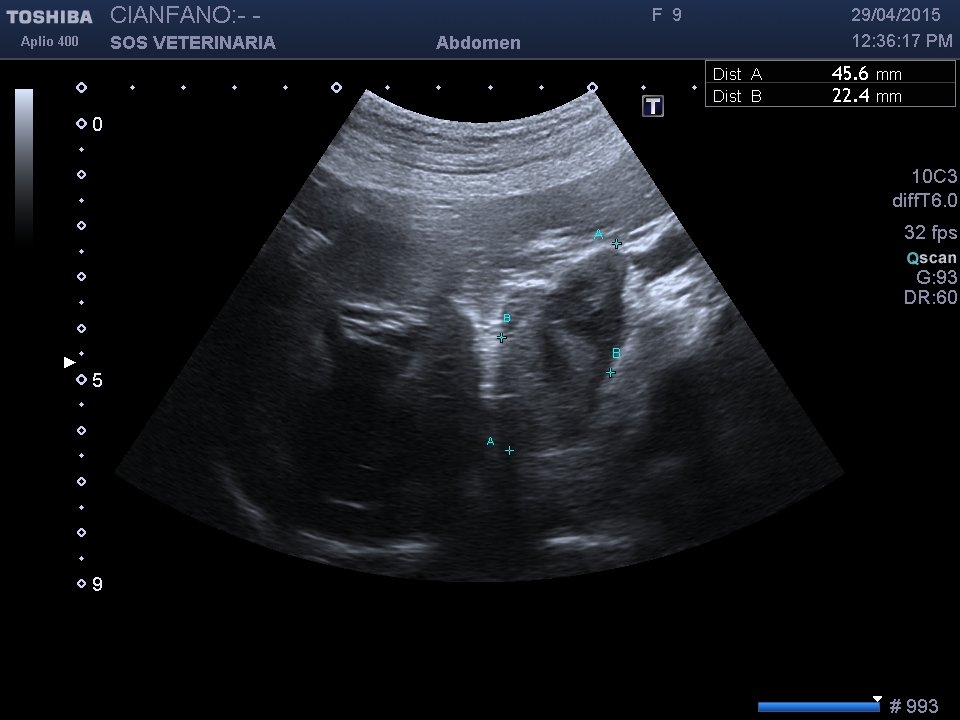

Buldog femmina di nome Giorgia durante un controllo di routine si visualizza una massa surrenalica destra con aspetti di invasione cavale . Giorgia sta bene nessun sintomo .

L’invasione cavale puo’ essere di tessuto neoplastico o iniziale formazione di un trombo.